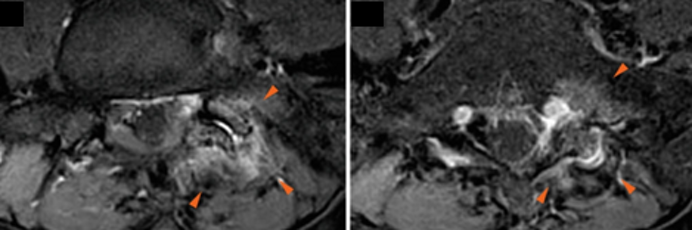

E’ in questi casi che si ricorre al trattamento più duraturo di questa sindrome: l’ablazione con radiofrequenza.

La tecnica consiste nel posizionare in corrispondenza del ramo dorsale del livello interessato un ago con elettrodo e attraverso una corrente sinusoidale di 400-500 kHz determinare un aumento della temperatura locale (superiore a 45 °C) e produrre la disattivazione delle fibre del ramo nervoso.

I risultati sono ottimi: tale procedura si rivela efficace nel 90 % dei casi.

La durata di azione può essere di definitiva anche se in alcuni casi, bisogna ripeterla a distanza di 12-18 mesi.

Gli effetti indesiderati sono rari (circa 1%) e includono disestesie e iperestesie cutanee circoscritte o, ancora più raramente un danno motorio o sensitivo, evitabile attraverso una stimolazione sensitiva e motoria, che precede ogni procedura di radiofrequenza.